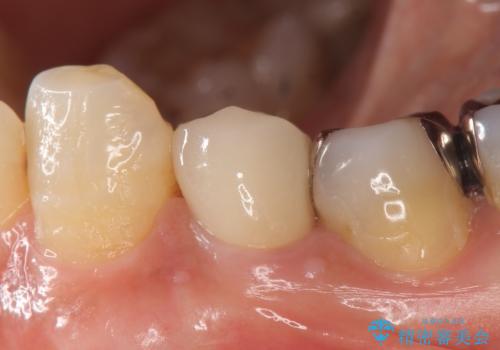

- 他院にて左下4の根管治療を行っていたが、疼くような痛みが引かないため当院にいらっしゃった方の症例です。

左下4の再根管治療を行い症状が治まったのち、オールセラミッククラウンによる補綴を行いました。

今回用いたオールセラミッククラウンはジルコニアフレームという白い素材の上にセラミックを盛っているため、審美性が非常に高いのが特徴です。

また、ジルコニアは人工ダイヤモンドの材料にも使われているほど高い強度を持っており、そのためオールセラミッククラウンは審美性だけでなく、奥歯やブリッジの補綴も可能とするクラウンです。